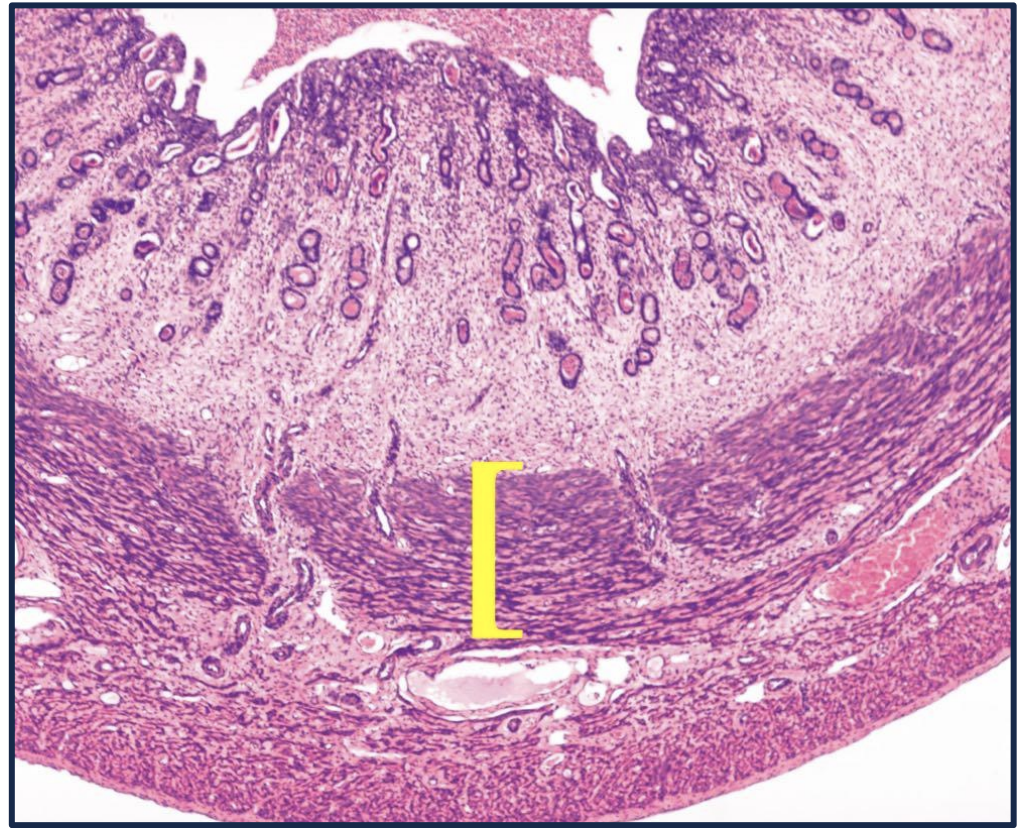

Q

What hormone influences this region of the uterus?

A

Oxytocin influences the myometrium